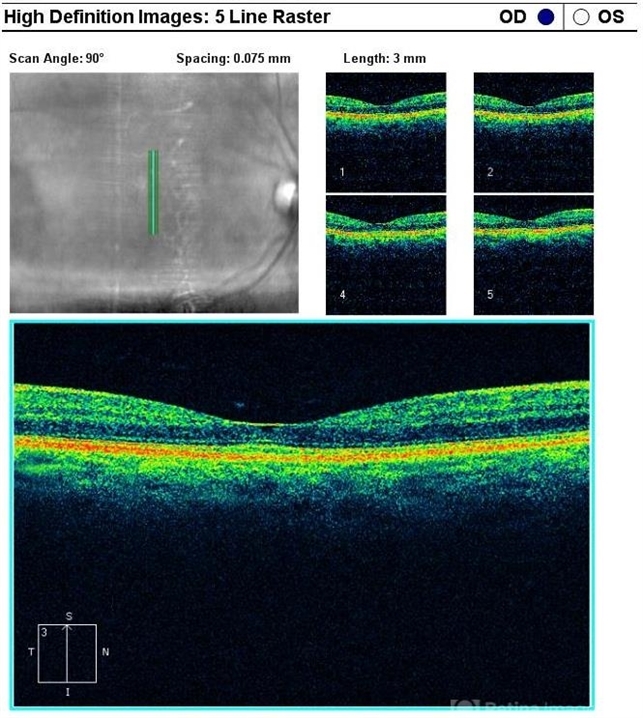

- Tamoxifen Maculopathy

- tamoxifen maculopathy, optical coherence tomography (OCT)

Optical coherence tomography system

Zeiss - Description

- A right eye OCT image of a 50-year-old patient treated with oral Tamoxifen for a period of over 4 years - showing atrophic central foveal cystic changes